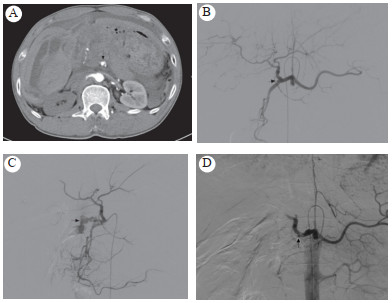

1 资料与方法病例1患者男,60岁。因上腹外伤(钢管击中)致疼痛不适2 h入院,无昏迷、呕吐、呕血、腹胀、便血、血尿。查体:血压90/50 mmHg(1 mmHg=0.133 kPa),心率120次/min,上腹部见皮肤擦痕,腹肌紧张,有反跳痛,肝脾肋下未及,肝区叩痛,移动性浊音阴性,肠鸣音低弱,血常规:血红蛋白70 g/L,红细胞1.98×1012/L。CT检查示肝左右叶挫裂伤,胰腺头颈部结构不清,密度不均,考虑有损伤,胃窦及十二指肠降部结构不清,胃十二指肠动脉近段斑点征及造影剂外溢(图 1A),盆腹腔积血。诊断:腹部损伤、胃十二指肠动脉损伤、肝挫裂伤、胰腺挫裂伤。给与输血补液扩容治疗同时急诊数字减影血管造影(digital substraction antiography, DSA):采用5F RH导管至腹腔动脉造影(philipsFD20 DSA机,碘海醇12 mL,速率4 mL/s,压力300 psi),造影示肝动脉走行正常,近胃十二指肠动脉处局部狭窄,未见明显造影剂外溢,胃十二指肠动脉开口处闭塞未显影(图 1B),行肠系膜上动脉造影示胰十二指肠下动脉近胃十二指肠动脉开口处见团块状造影剂外溢(图 1C),泰尔茂2.7 F微导管超选至近动脉破裂处,使用COOK 2~4 mm微钢圈2个栓塞后复查造影示造影剂外溢消失(图 1D),患者血压回升113/83 mmHg,心率下降至90次/min。术后保守治疗,未见复发出血,术后患者有低热、恶心、呕吐、腹痛、腹胀等表现,经对症处理后好转,未发生消化道出血胃肠道坏死或穿孔。

| A:胃十二指肠动脉近段斑点征及造影剂外溢;B:肝动脉狭窄,胃十二指肠动脉开口处闭塞未显影;C:胰十二指肠下动脉造影剂团块状外溢;D:微钢圈栓塞后造影剂外溢征消失 图 1 病例1的CT和造影检查结果 |